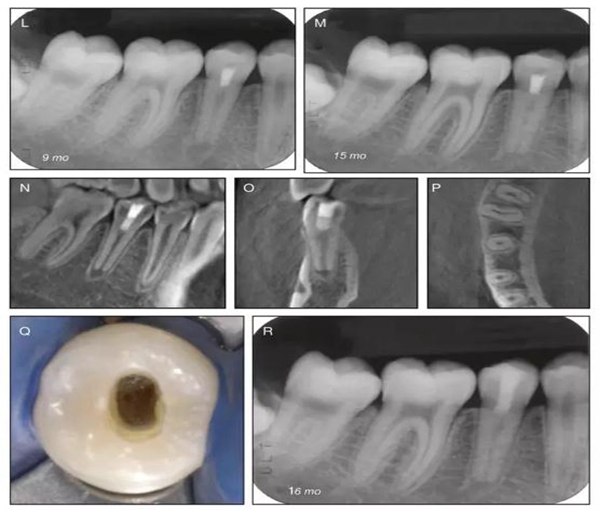

原則上年輕恒牙的牙髓治療應(yīng)盡可能以保存活髓的方式以便不影響牙根繼續(xù)發(fā)育。本文3個(gè)病例均描述了根尖尚未發(fā)育完成的下頜前磨牙被確診為牙髓壞死伴有大面積根尖病損,治療過程中在根管內(nèi)發(fā)現(xiàn)了部分活髓,而采用活髓切斷后都取得了很好的療效。